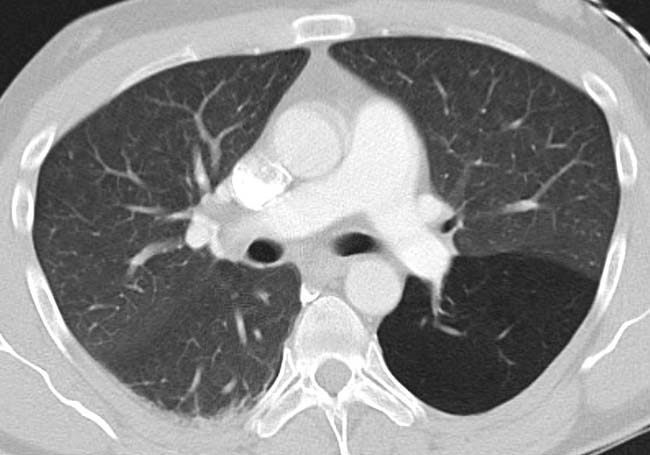

Contributors: Travis Barlock MD, Jeffrey Olson MS4 Feel free to use the cases below for your own practice. All of the scenarios are completely made up and designed to hit several teaching points. Case 1 25 M, presents to the ED with chest pain. Stabbing, started a few hours ago, substernal. Thinks it is GERD. After 2-3 minutes, pain worsens and radiates to the back. VS: BP 125/50 (Right arm 190/110). HR 120. RR of 18. Sat 98% on RA. Additional VS: Temp of 37.2, height of 6'5", BMI of 18. PMH: None, doesn't see a doctor. Meds: None FH: Weird heart thing (Mitral Valve Prolapse), weird lung thing (spontaneous pneumothorax), tall family members with long fingers and toes Physical Exam: Cards: Diastolic decrescendo at the RUSB, diminished S2. UE pulses are asymmetric, LE pulses are asymmetric, carotid pulses are asymmetric, BP is asymmetric MSK: Knees, elbows, and wrists are hypermobile. Imaging: CXR #1 normal, #2 widened mediastinum (no read yet but shows widened mediastinum), POCUS shows small effusion CTA/MRA doesn't come back until after the case. ECG: Sinus Tach Labs: NT-proBNP 500 pg/mL D-Dimer: 7000 ng/L CBC: Hemoglobin: 13.5 g/dL, WBC: 20,000/µL, Platelets: 250,000/µL Chem 7: Na 138, K, 5.7, Cl 102, Bicarb 17, BUN 45, Creatinine: 3.5 mg/dL, Glucose: 180 LFTs: Albumin 2.4, Total protein 5.5, ALP: 140, AST: 3500, ALT: 2800, TBili: 3.2, DirectBili: 2.4, Ca: 7.8 LDH: 2200 PT: 20.5, INR: 2.2, Fibrinogen: 170 5th gen High-Sensitivity Troponin: <3 Lactate: 7 mmol/L VBG: pH 7.22, paCO2 28, bicarb 15 Notes: Can have patient crash somewhere in middle and show 2nd xray Case 2: A 67-year-old female is brought to the ED by her daughter due to progressive weakness, confusion, and fatigue that have worsened over the past week. Unable to get out of bed and has become increasingly lethargic. Also having some nausea, constipation. The daughter denies any preceding illness, recent trauma, or travel. Does not know her meds but will head home to get them after talking with you. VS: BP 88/55 mmHg, HR 110, RR 20, O2 Sat 98% on room air. Additional VS: Temp 36.8°C. PMH: Hypertension, osteoarthritis, and depression. Physical exam: General: Thin, somnolent but arousable. HENT: Dry mucous membranes Neuro: Confused, A&Ox1 (self), hyporeflexia Labs (Includes many that would not return in the ED in case you want to take this case forward to the floor) CBC: WBC 9,500, Hb 16.5, Hct: 50%, Platelets 220,000 Chem7: Na 129, K 2.1, Cl 95, HCO3 34, Creatinine 1.6, BUN 40, Glucose 115 LFTs: normal Magnesium: 1.1 Calcium: 10.8 mg/dL (corrects to 12.8) iCal: 3.2 Phosphate: 2.3 mg/dL Albumin: 2 BUN:Cr ratio: 25 VBG: pH: 7.49, PaCO2 45, HCO3: 34 Lactate: 2.8 Serum Osmolality: 276 mOsm/kg (Osmolal gap of 2) Urine Osmolality: 550 mOsm/kg Urine Sodium (UNa): 10 mEq/L (low). Urine Potassium (UK): 25 mEq/L (elevated). Urine Chloride (UCl): 12 mEq/L (low). Urine Magnesium (UMg): 20 (Elevated). Urine Calcium (UCa): 50 in 24 hrs (Low) 100 cc of urine with foley FeNa Plasma renin activity: 15 mg/mL/hr (elevated), Aldosterone: 25 ng/dL (Elevated), ADH: Elevated, Diuretic screen: Positive for thiazides PTH: 8 (low), HsTrop: 32, Cortisol and ACTH: Normal. EKG: Hypokalemia features CXR: Normal Renal US: shows stones Improves with fluids Note: Can have daughter return with med list at some point including HCTZ, ibuprofen, and sertraline Case 3: Patient Presentation EMS Report: A 27-year-old male involved in a high-speed motorcycle collision is brought to the emergency department by EMS. The patient was found unconscious at the scene with evidence of severe thoracic and extremity trauma. He was intubated en route for airway protection due to altered mental status (GCS 7). VS: HR 130, BP 90/60, RR: bagging at 12 bpm, satting 88% on 100% FiO2 Primary Survey Airway: Endotracheal tube in place. Breathing: Decreased breath sounds on the left side with visible chest asymmetry and paradoxical chest wall movement. Circulation: Mottled extremities noted, with significant deformity of the right thigh. Pulses are diminished in the right leg Disability: GCS remains 7 (E1 V2 M4). Pupils equal and reactive. Exposure: Full-body examination reveals an open fracture of the right femur, multiple abrasions, and bruising over the chest wall. Vent alarms Peak Inspiratory Pressure (PIP) 40 cm H₂O (elevated) Plateau Pressure (Pplat) 35 cm H₂O (elevated) EtCO₂ (End-Tidal CO₂) 55 mmHg High-Pressure Alarm Triggering frequently Glucose 120 CBC: Hgb 8.9, Hct 27, WBC 14.2, platelets 220,000 VBG: pH 7.28, pCO2 33, bicarb 18, lactate 4.5 CXR with tension pneumothorax Patient improves after chest tube, pigtail catheter, or needle decompression. Ready to be transferred upstairs and O2 starts tanking again Vent alarms- second episode Peak Inspiratory Pressure (PIP) 35 cm H₂O (elevated) Plateau Pressure (Pplat) 30 cm H₂O (elevated) EtCO₂ (End-Tidal CO₂) 20 mmHg HR: 140, satting 84%, temp 38.5, ABG: pH 7.32, pCO₂ 30 mmHg, pO₂ 60 mmHg on 100% FiO₂, HCO₃⁻ 18 mmol/L (hypoxemia and metabolic acidosis). D-dimer: Elevated Thrombocytopenia: Platelets 90,000/µL. US shows blown right ventricle ECG shows new RBBB CT PE: Ground glass opacities, consolidation, centrilobular nodules, septal thickening, and fat-attenuating lesions. Note: Management is largely supportive care so once the diagnosis is made, end the case. References Carroll MF, Schade DS. A practical approach to hypercalcemia. Am Fam Physician. 2003 May 1;67(9):1959-66. PMID: 12751658. Coelho SG, Almeida AG. Marfan syndrome revisited: From genetics to the clinic. Rev Port Cardiol (Engl Ed). 2020 Apr;39(4):215-226. English, Portuguese. doi: 10.1016/j.repc.2019.09.008. Epub 2020 May 18. PMID: 32439107. Palmer BF. Metabolic complications associated with use of diuretics. Semin Nephrol. 2011 Nov;31(6):542-52. doi: 10.1016/j.semnephrol.2011.09.009. PMID: 22099511. Reed MJ. Diagnosis and management of acute aortic dissection in the emergency department. Br J Hosp Med (Lond). 2024 Apr 30;85(4):1-9. doi: 10.12968/hmed.2023.0366. PMID: 38708978. Roberts DJ, Leigh-Smith S, Faris PD, Blackmore C, Ball CG, Robertson HL, Dixon E, James MT, Kirkpatrick AW, Kortbeek JB, Stelfox HT. Clinical Presentation of Patients With Tension Pneumothorax: A Systematic Review. Ann Surg. 2015 Jun;261(6):1068-78. doi: 10.1097/SLA.0000000000001073. PMID: 25563887. Rothberg DL, Makarewich CA. Fat Embolism and Fat Embolism Syndrome. J Am Acad Orthop Surg. 2019 Apr 15;27(8):e346-e355. doi: 10.5435/JAAOS-D-17-00571. PMID: 30958807. Produced by Jeffrey Olson, MS4 Special thanks to Evan Fisch MD Get your tickets to Tox Talks Event, Sept 11, 2025: https://emergencymedicalminute.org/events-2/ Donate: https://emergencymedicalminute.org/donate/